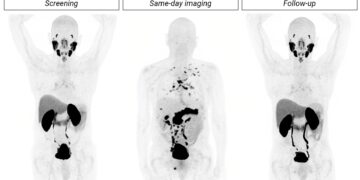

PR Newswire SABRE topline results: Cu-64 SAR-Bombesin is effective in detecting prostate cancer recurrence in patients with negative SOC imaging by Money Compass June 13, 2025